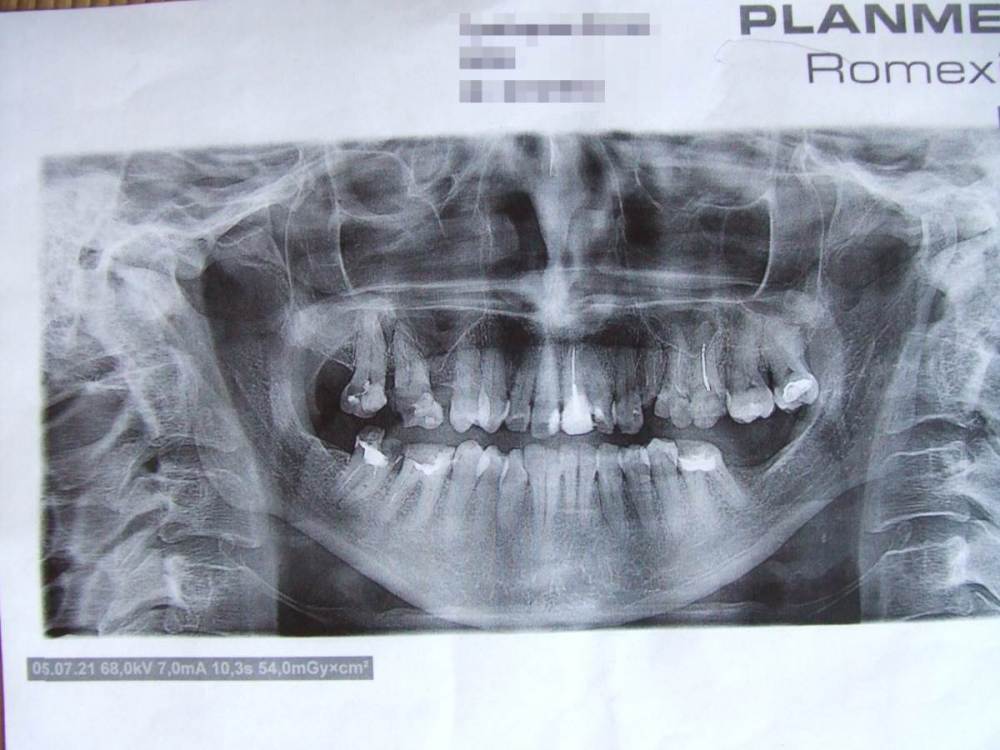

Moscowhelen Опубликовано 2 августа, 2022 Автор Поделиться Опубликовано 2 августа, 2022 Снимок челюсти сделан 2021. Ссылка на комментарий

Moscowhelen Опубликовано 2 августа, 2022 Автор Поделиться Опубликовано 2 августа, 2022 Возраст мой 49 лет. На данный момент удалены 1.5,2.4,3.7,4.6,4.7 зубы. Ссылка на комментарий